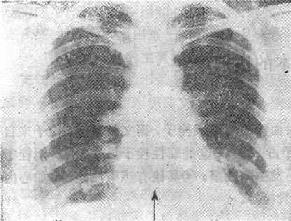

肺梗死

图116-1 肺梗死